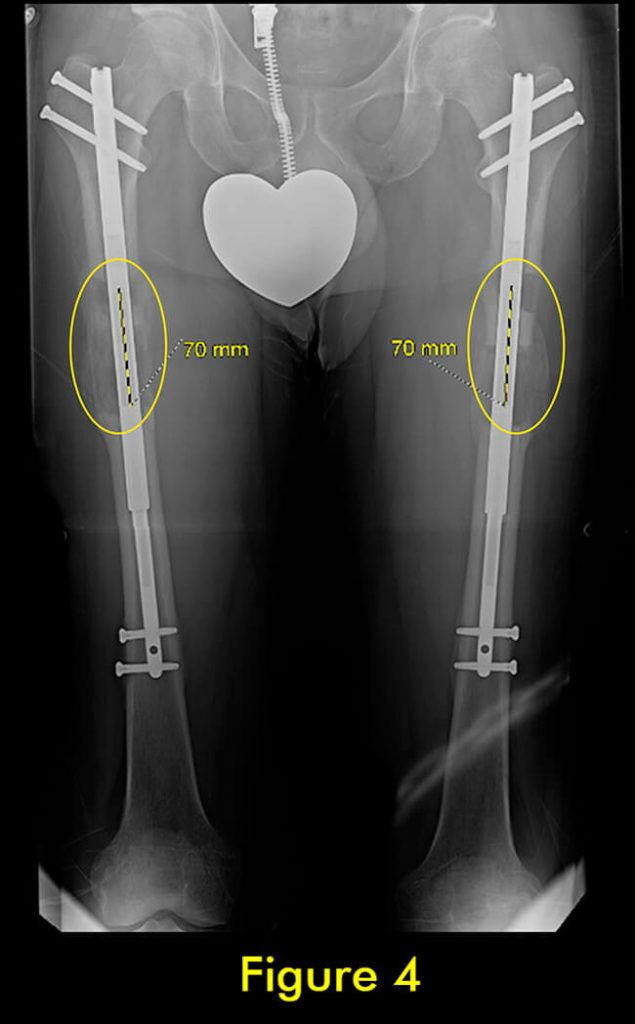

过早合并示意图1

图1:延长量细微差异

过早合并示意图2

图2:X光片确认诊断

过早合并示意图3

图3:重复截骨术

过早合并示意图4

图4:完全巩固